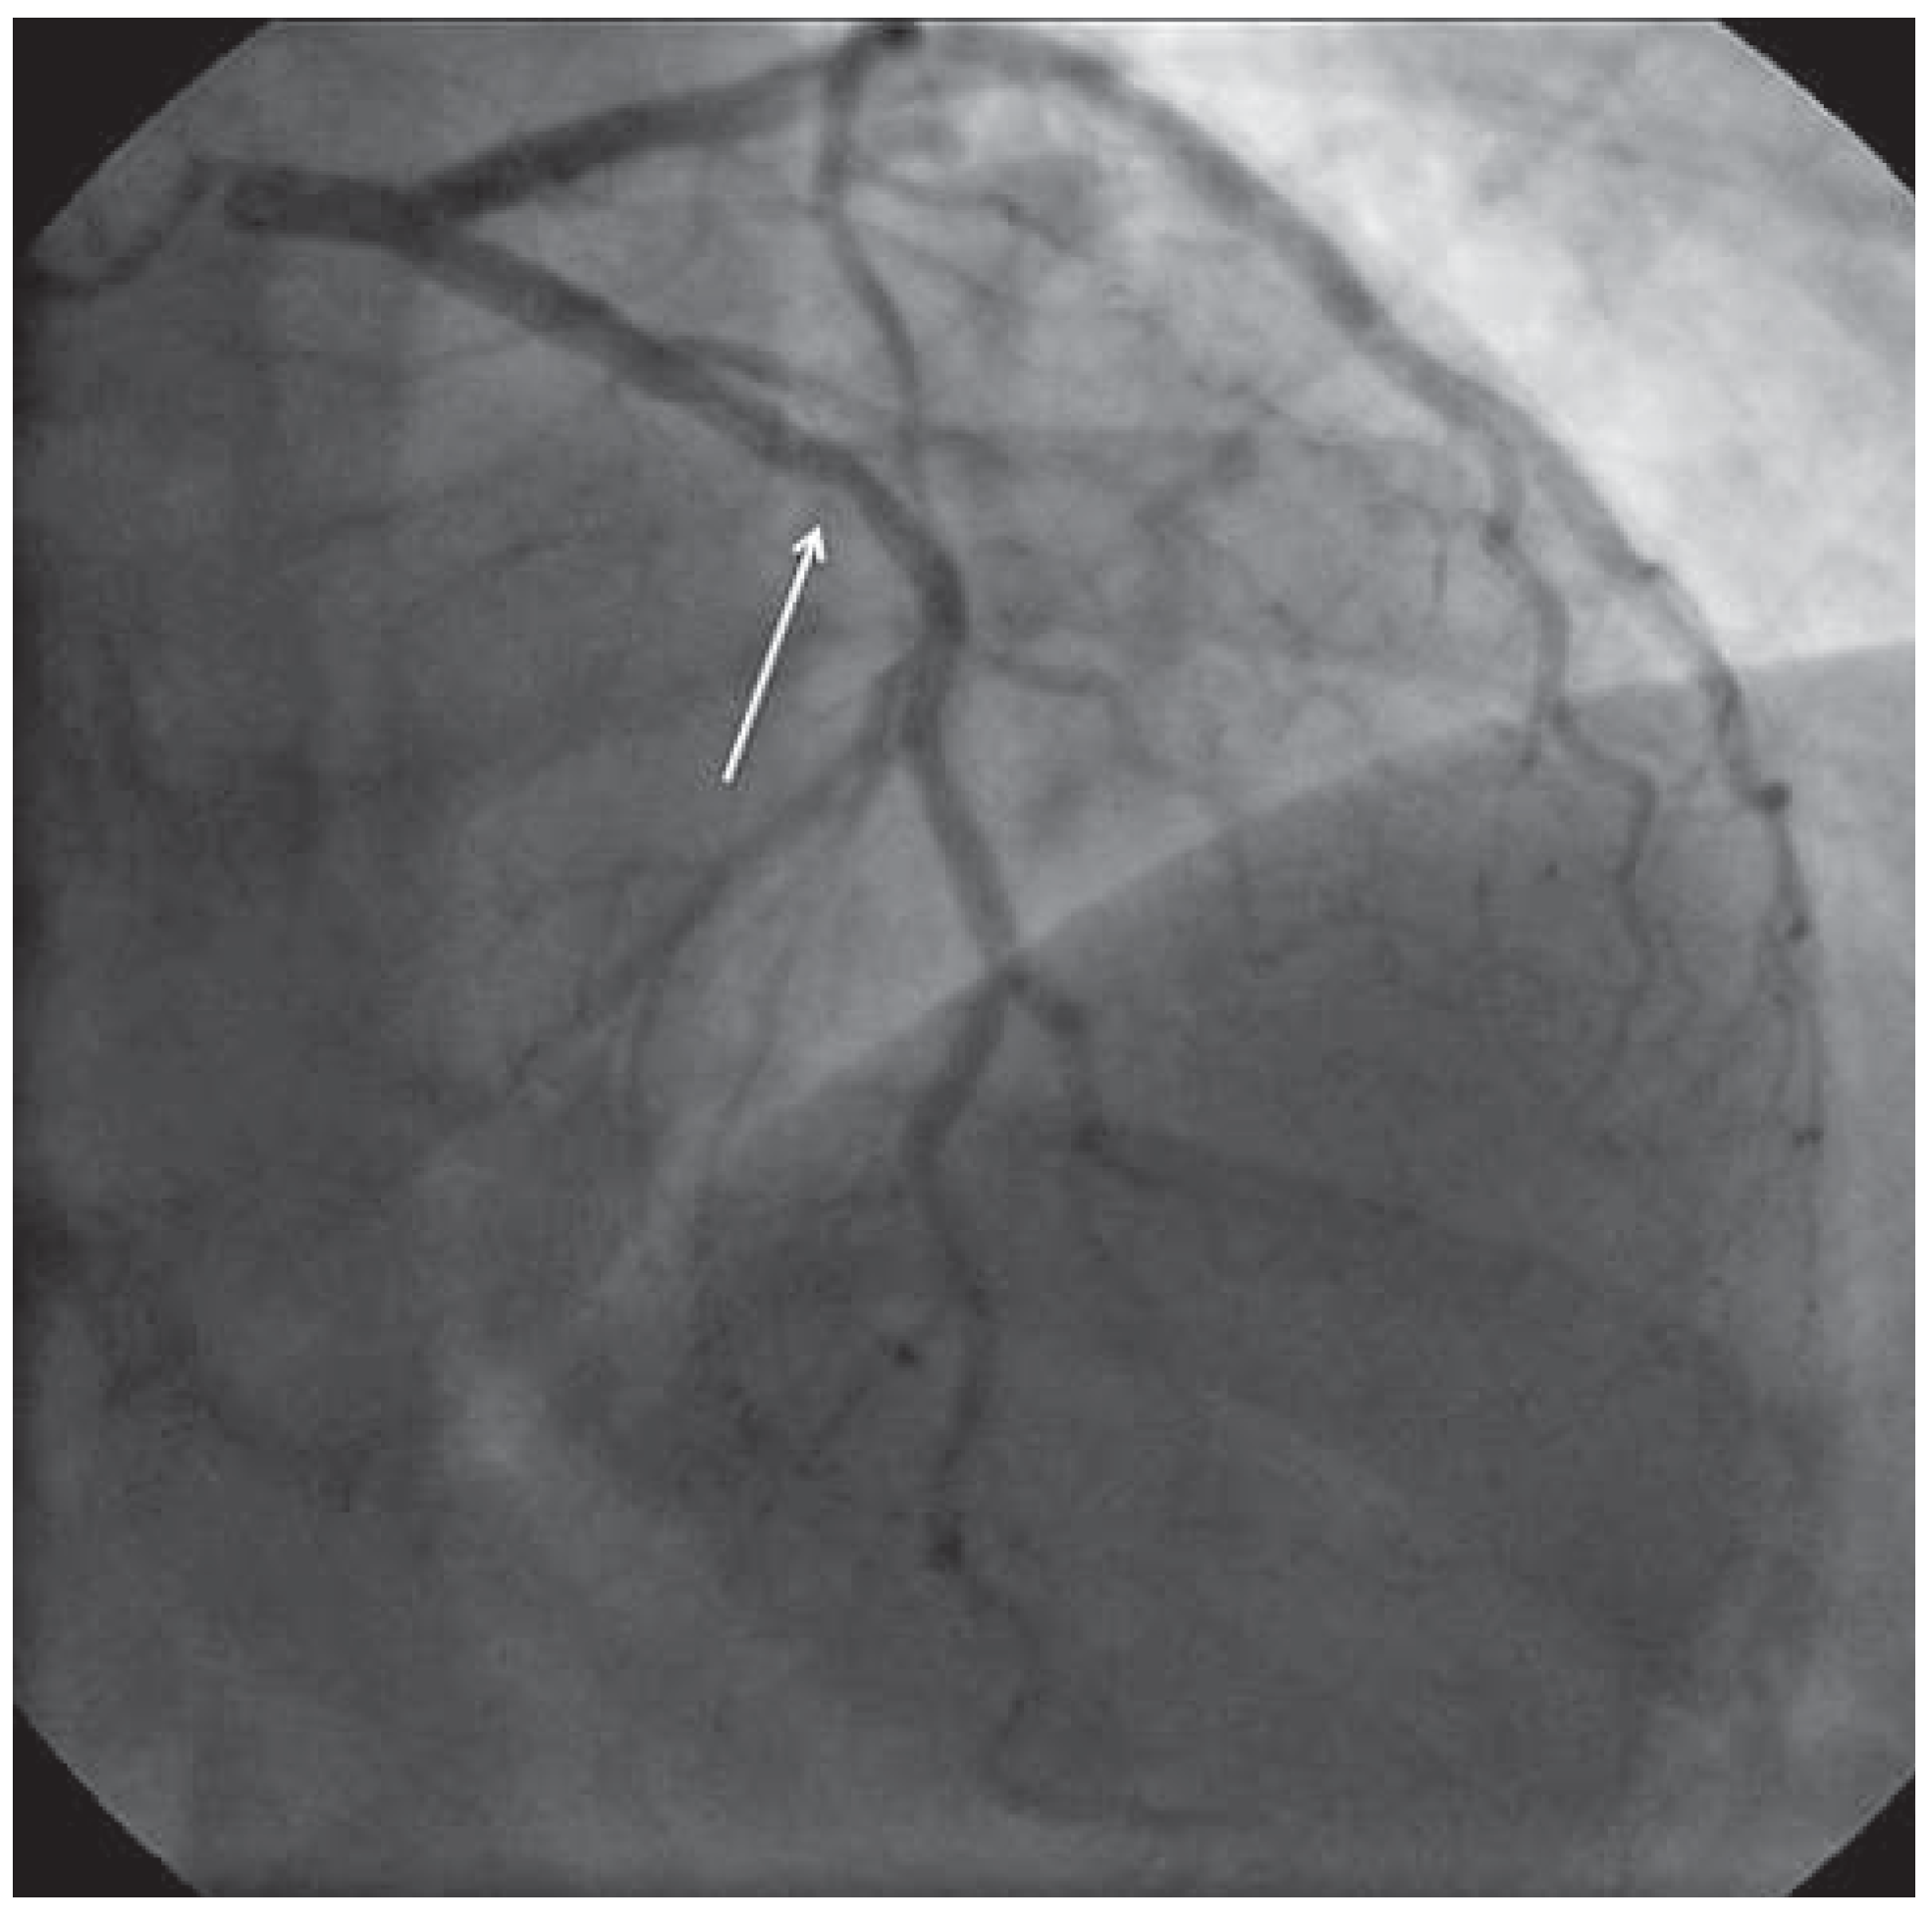

Case report